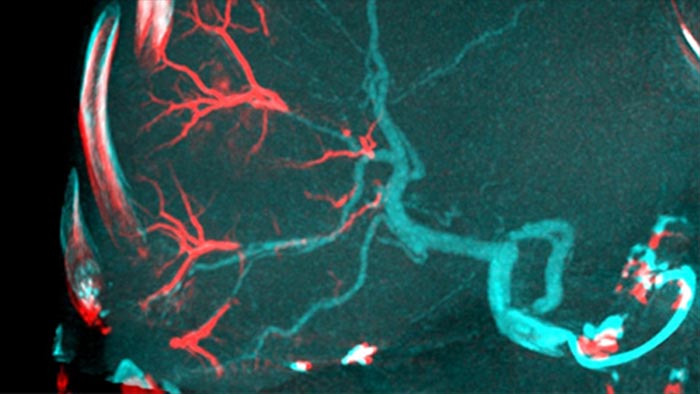

Détection automatique des vaisseaux nourriciers avec EmboGuide.

Détection automatique des vaisseaux nourriciers avec EmboGuide

Notre solution de détection automatique des vaisseaux nourriciers améliore de manière significative la détection des artères nourricières par rapport à l’utilisation de la tomographie à faisceau conique seule. EmboGuide vous aide à maximiser l’efficacité de vos procédures de chimio-embolisation transartérielle en améliorant votre sensibilité, en réduisant les faux positifs et en maximisant la concordance entre les lecteurs .1